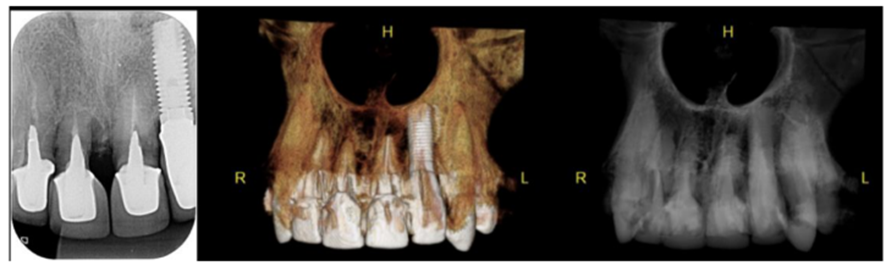

A fim de discutirmos com mais afinco este tópico, apresentamos um caso clínico bastante interessante da região anterior superior, onde o paciente foi perdendo dentes e colocando implantes ao longo de oito anos. As figuras 1 a 4 ilustram o caso.

Apesar das imagens radiográficas denunciarem os problemas ósseos do dente 11, foi o elemento 21 que fraturou primeiro, fazendo com que iniciássemos a reabilitação com implantes apenas no elemento 21, pois o paciente queria manter os seus demais dentes a todo custo.